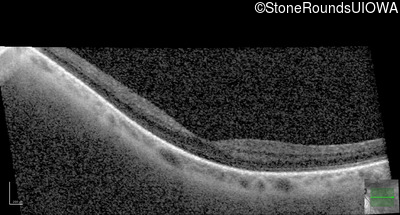

OCT Stack